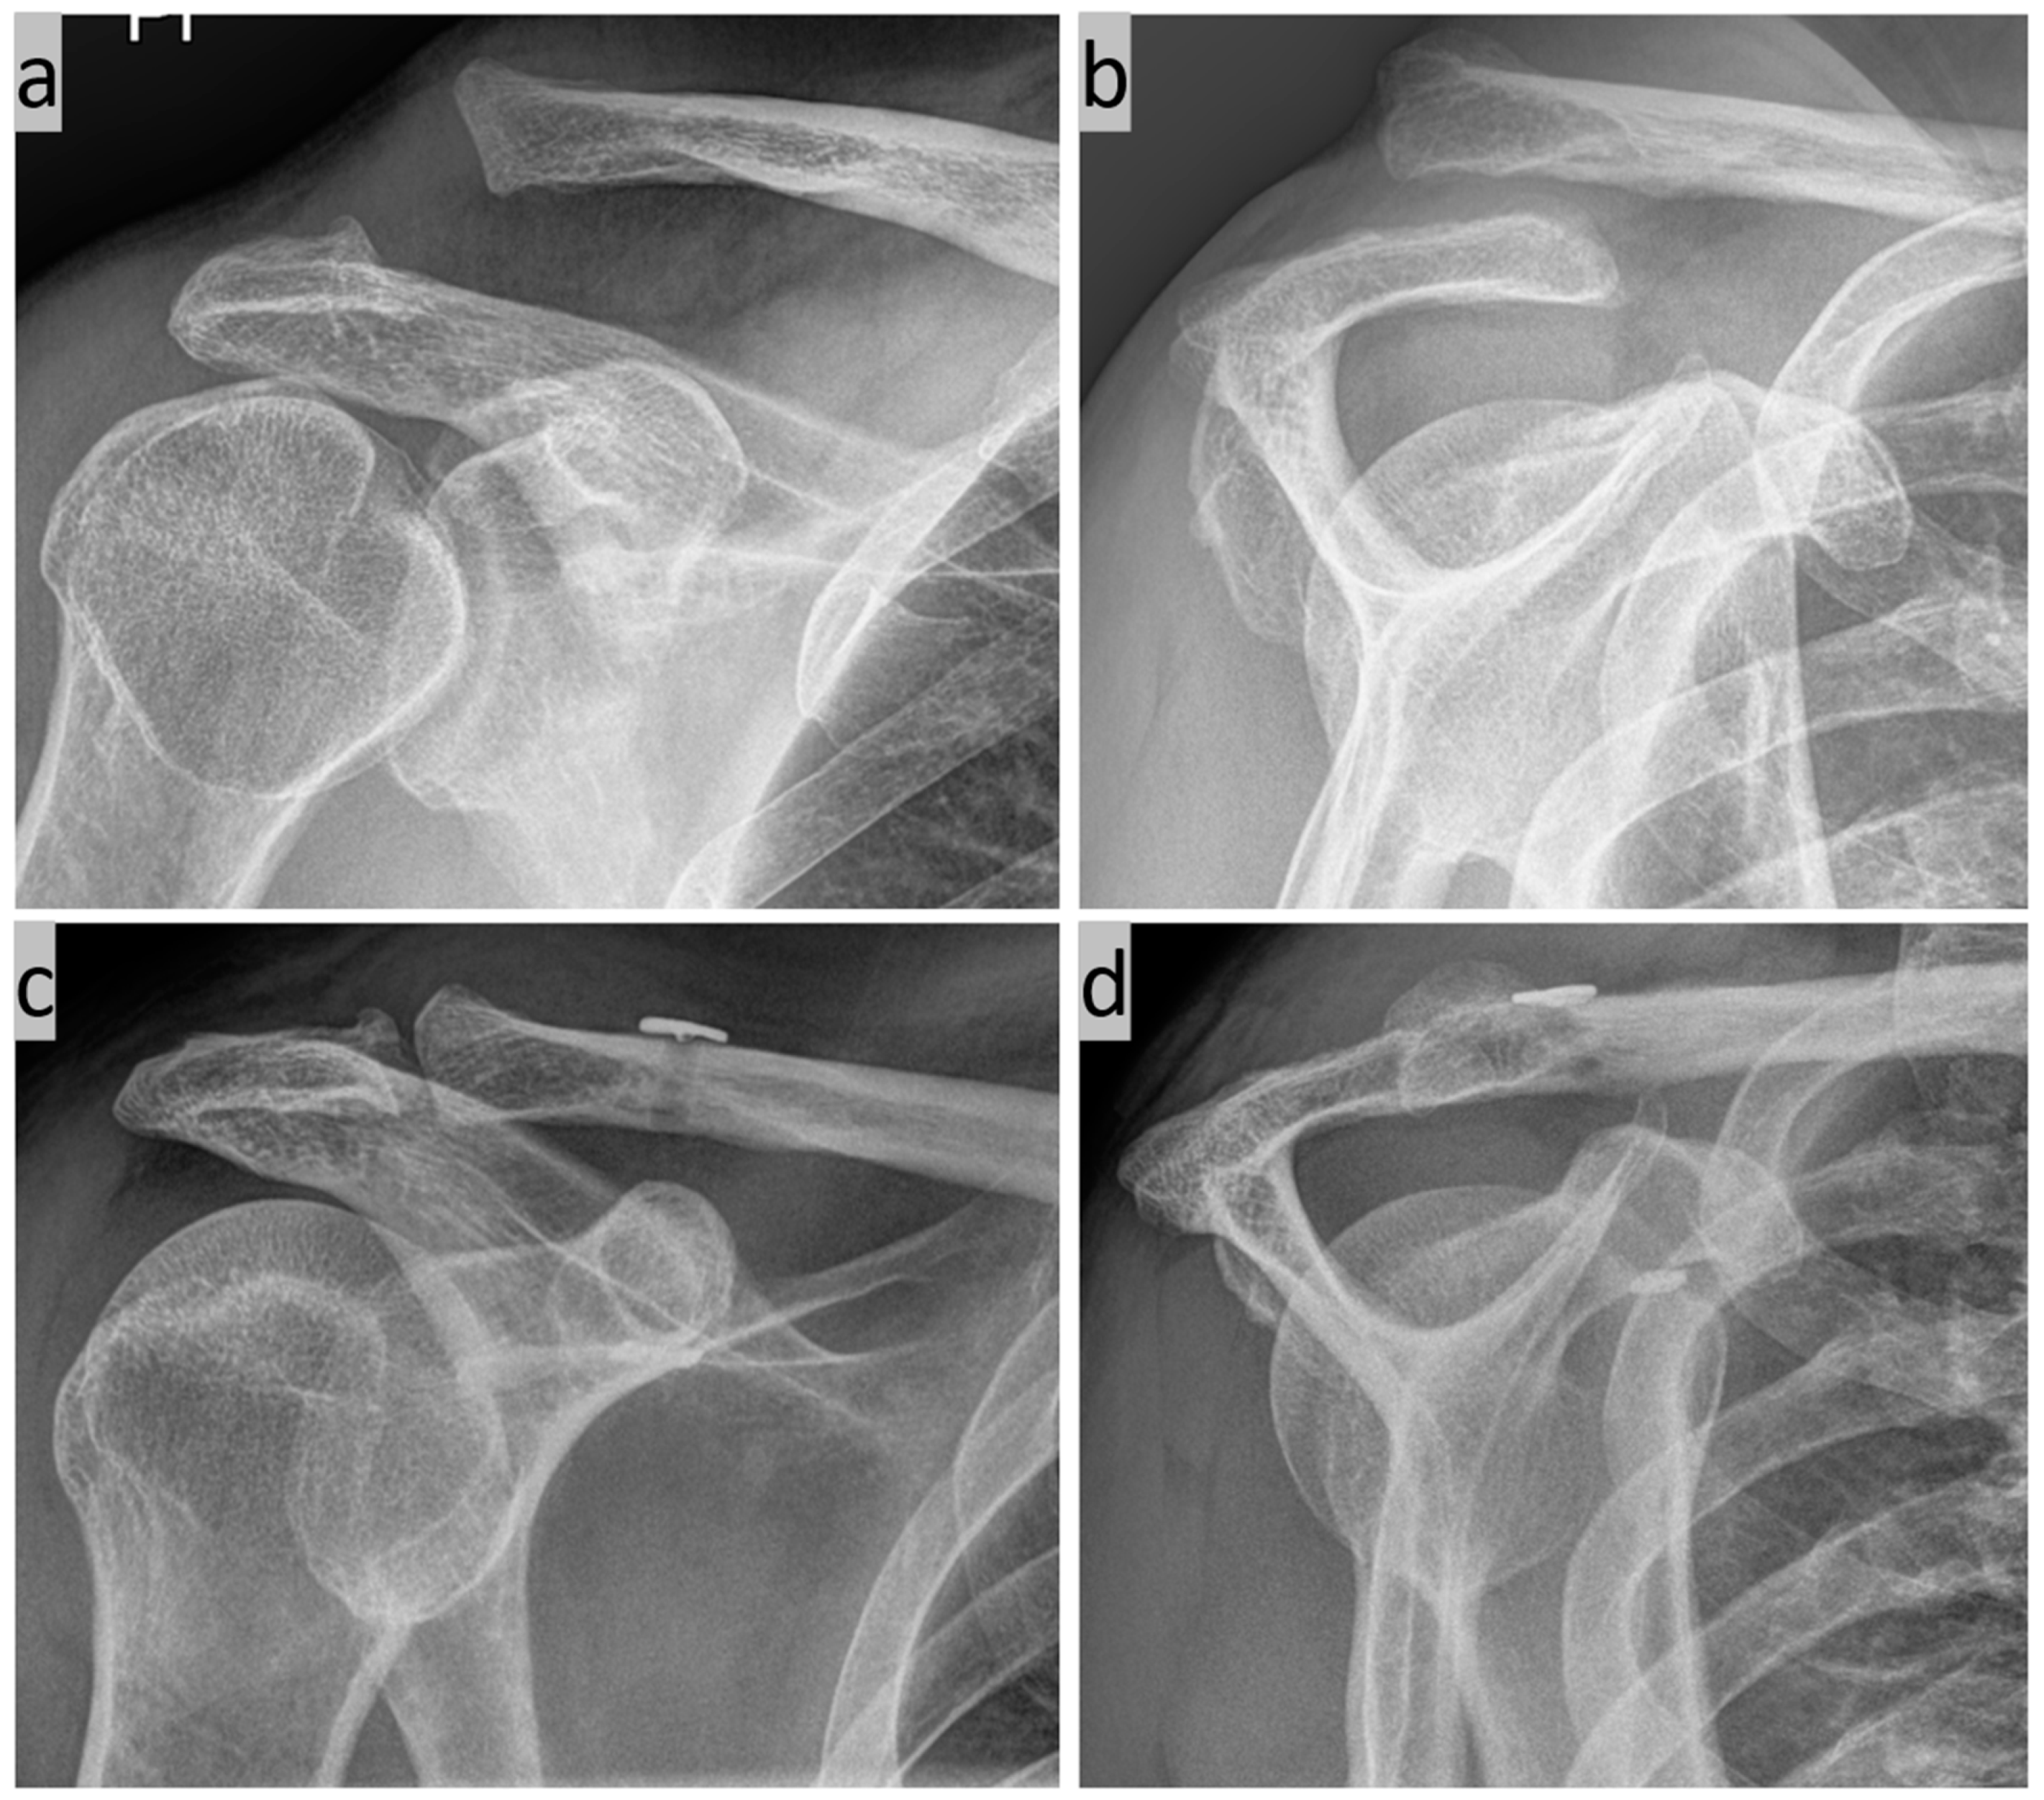

2. Surgical Technique

- Böhringer, A.; Gebhard, F.; Dehner, C.; Eickhoff, A.; Cintean, R.; Pankratz, C.; Schütze, K. 3D C-arm navigated acromioclavicular joint stabilization. Arch. Orthop. Trauma. Surg. 2023, 144, 601–610. [Google Scholar] [CrossRef]